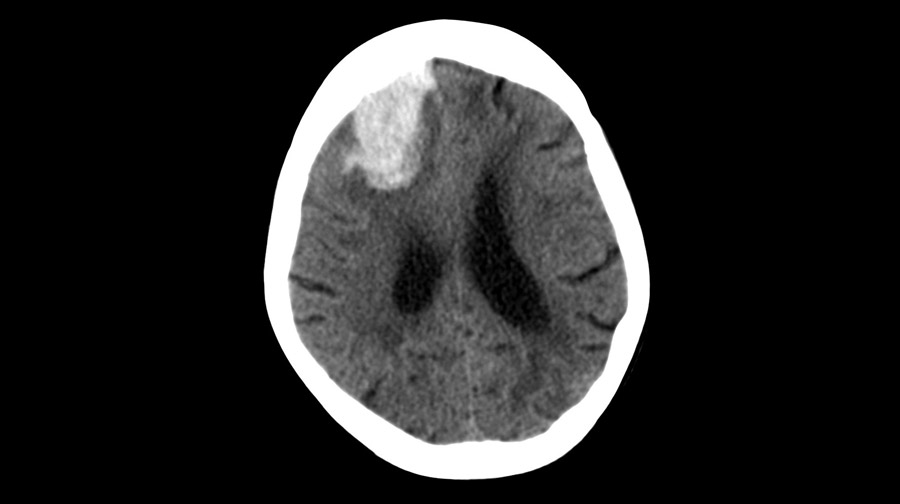

En los pacientes en quienes la cirugía se pudo realizar dentro de las 24 horas posteriores a una hemorragia intracerebral aguda, la evacuación mínimamente invasiva del hematoma produjo mejores resultados funcionales a los 180 días que el tratamiento médico basado en guías. El efecto de la cirugía parece atribuirse a la intervención de las hemorragias lobares. New England Journal of Medicine, 10 de abril de 2024.